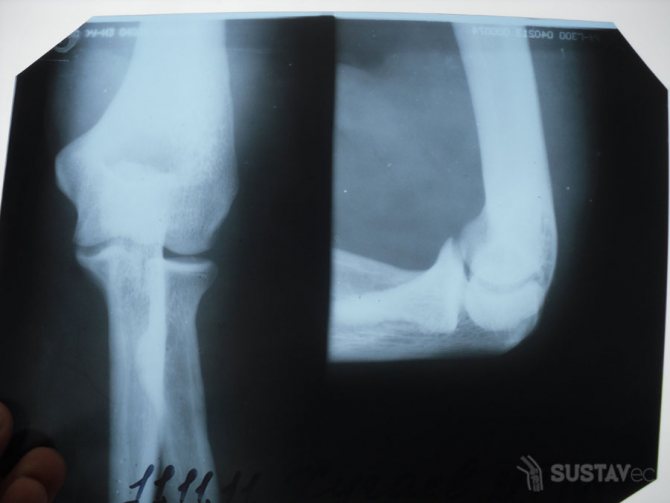

При переломах возникают сильные боли, повреждаются нервы, сосудистые ткани, рука становится менее чувствительной. Требуется восстановить целостность костных структур, проводят обезболивание, накладывают гипсовую повязку. Срок ношения гипса зависит от тяжести травмы. После снятия гипсовой повязки требуется разработка сустава, применяют физиотерапию с лечебной физкультурой.

- Рентгеновский снимок, чтобы исключить патологию сердечной мышцы, позвоночника и локтевого сустава.

Для объективного анализа проводится рентгенография для выявления дегенерации тканей, магнитно-резонансная томография для оценки мягких тканях. При недостаточной информативности предыдущих способов назначается артроскопия, позволяющая исследовать суставную поверхность изнутри, а также диагностическая пункция с забором выпота для определения возбудителя инфекции.

- Рентгенография. Помогает определить повреждения костной ткани.

Пациент должен иметь в виду, что лечение предполагаемого перелома, вывиха или растяжения может назначаться только после получения результатов рентгенографии, а никак не раньше. Благодаря соблюдению всех рекомендаций врача больной может полностью излечиться от заболевания, если оно находится в ранней стадии. Запущенную патологию кисти или локтя лечить очень сложно, а порой просто невозможно.